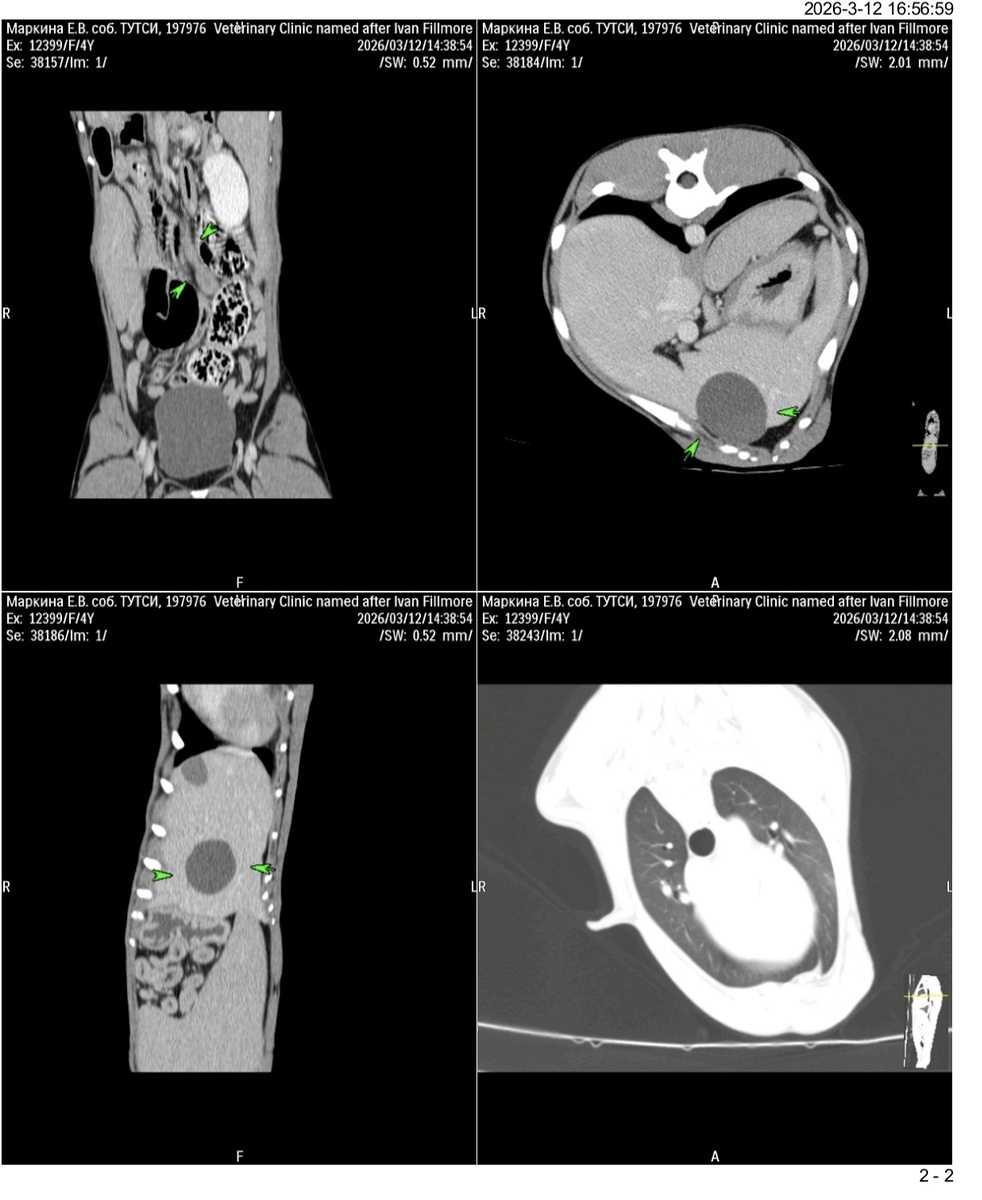

По заключению КТ новости у нас не очень:

-Образование молочных желез 3 пакета справа и слева, признаки серомы по месту шва белой линии

-признаки микроузелков в лёгких

-признаки кисты в печени

-признаки спленомегалии

-признаки аденомегалии лимфоузлов брюшной полости, забрюшинного пространства и тазовой области

Заключение я с утра отправила нашему хирургу, будем думать и принимать решение об операции.

С такими вводными данными, на 99 процентов после хирургии понадобится химиотерапия.